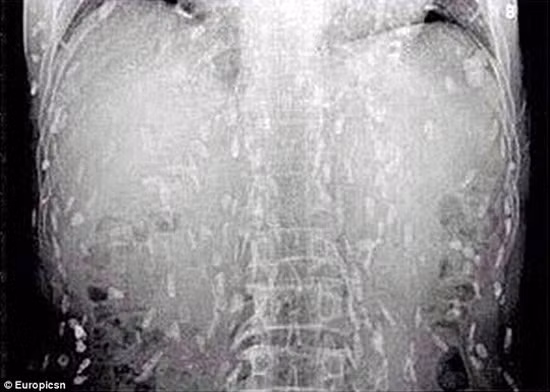

Một người đàn ông Trung Quốc nghiện sushi tìm đến bác sĩ trong tình trạng đau bụng và ngứa da. Ông bị sốc khi biết giun sán ký sinh là nguyên nhân của tình trạng này. Ảnh chụp X-quang cho thấy sán có ở toàn thân bệnh nhân.

Daily Mail ngày 5-6 đưa tin người đàn ông Trung Quốc tìm đến Bệnh viện Nhân dân Số 8 ở Tỉnh Quảng Đông, Trung Quốc phàn nàn về chứng đau dạ dày và ngứa da trong thời gian dài. Sau khi quét toàn bộ cơ thể, các bác sĩ đã nhận được hình ảnh khá kinh dị: Cơ thể bệnh nhân dày đặc giun sán

Tiến sĩ Yin từ Bệnh viện Nhân dân số 8 Quảng Châu nói rằng ăn thức ăn chưa nấu chín nhiễm trứng sán dây sẽ gây ra bệnh giun sán. Khi trưởng thành, sán có thể đi vào máu người, nếu lên não có thể gây tử vong. Nhìn hình X-quang, có lẽ nhiều người không bao giờ dám ăn cá sống.

Tại sao cơ thể người đàn ông có thể biến thành tổ sán chi chít như vậy? Một khi người nhiễm bệnh, sán dây sẽ phát triển bên trong ruột người với chiều dài lên đến 15 mét chỉ trong một vài tuần. Sán có thể tồn tại nhiều tháng, nhiều năm trong cơ thể người mà không bị phát hiện, sau đó lần lượt để trứng trên khắp cơ thể người.